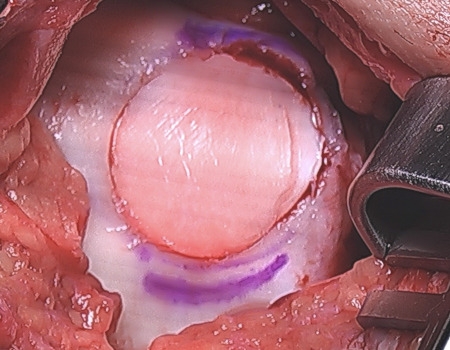

OATs Implantation

Implanted OATs

Arthroscopic View of Implanted OATs